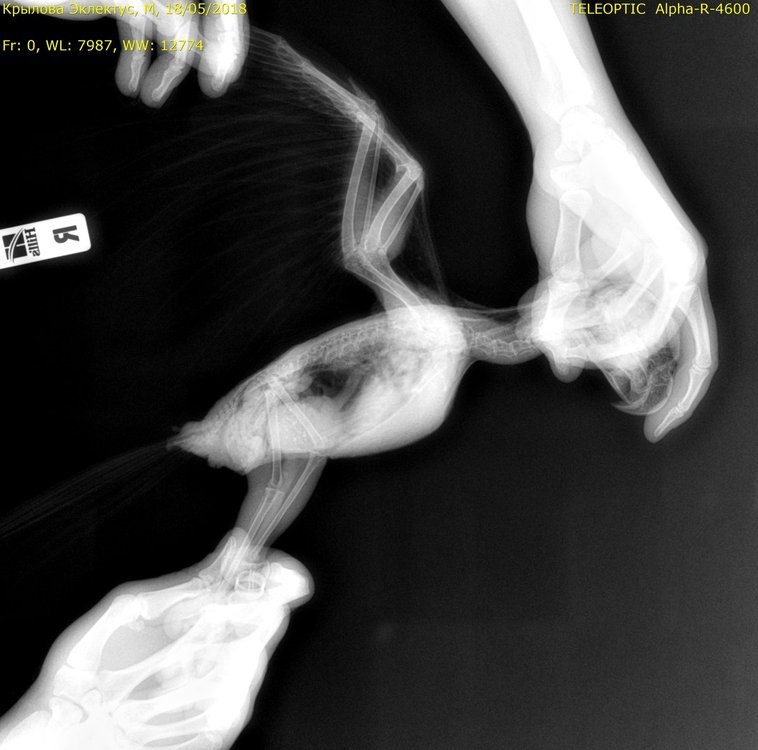

Shiny_Jey Опубликовано 21 мая, 2018 Автор #14 Опубликовано 21 мая, 2018 Сделали рентген, копрограмму и ОАК. По рентгену предположили аспергиллез... Но еще не видя результатов анализов. Вроде почитала, что при нем лейкоциты понижаются, а у Гоши сильно повышены.

Shiny_Jey Опубликовано 31 мая, 2018 Автор #15 Опубликовано 31 мая, 2018 (изменено) Отпишусь в теме своей птички. По рентгену действительно Зося предполагает аспергиллез или клебсиелльную пневмонию или туберкулёз. 22 мая начали: Доксициклин 2 раза в день по 0,25 мл растворенной капсулы на 5 мл воды. Т.е. суточная доза 10 мг Итраконазол 2 раза в день по 21 гранулке ( в капсуле 100 мг 1200 гранул) так что суточная доза 3 мг. Секстафаг 1 раз в день 0,5 мл. Карсил, пивные дрожжи, Хилак форте 9 капель в поилку. 26.05 добавила Бифидумбактерин, т.к. помёт был плох. Ещё надо давать иммуномодулятор, никак не начну... Зашла почитать как давать фоспренил, и тоже в клюв... Хотелось бы что-то менее точное, т.к. и так антибиотики два раза в день. Фоспренил, имунофан, ещё Мелоксикам тоже не начала, не спросила дозировку. По состоянию: попугай обрастает перьями, самоощип явно вызван линькой был, но хорошо, что обратил внимание на такую серьезную болячку. Из того, что внушает опасение- много дрожит( лапы НЕ горячие), сидит на одной лапе ( или это хорошо?) Вес прибавил: было 380 грамм, сегодня 400. Хотя за весом надо последить. Изменено 31 мая, 2018 пользователем Shiny_Jey